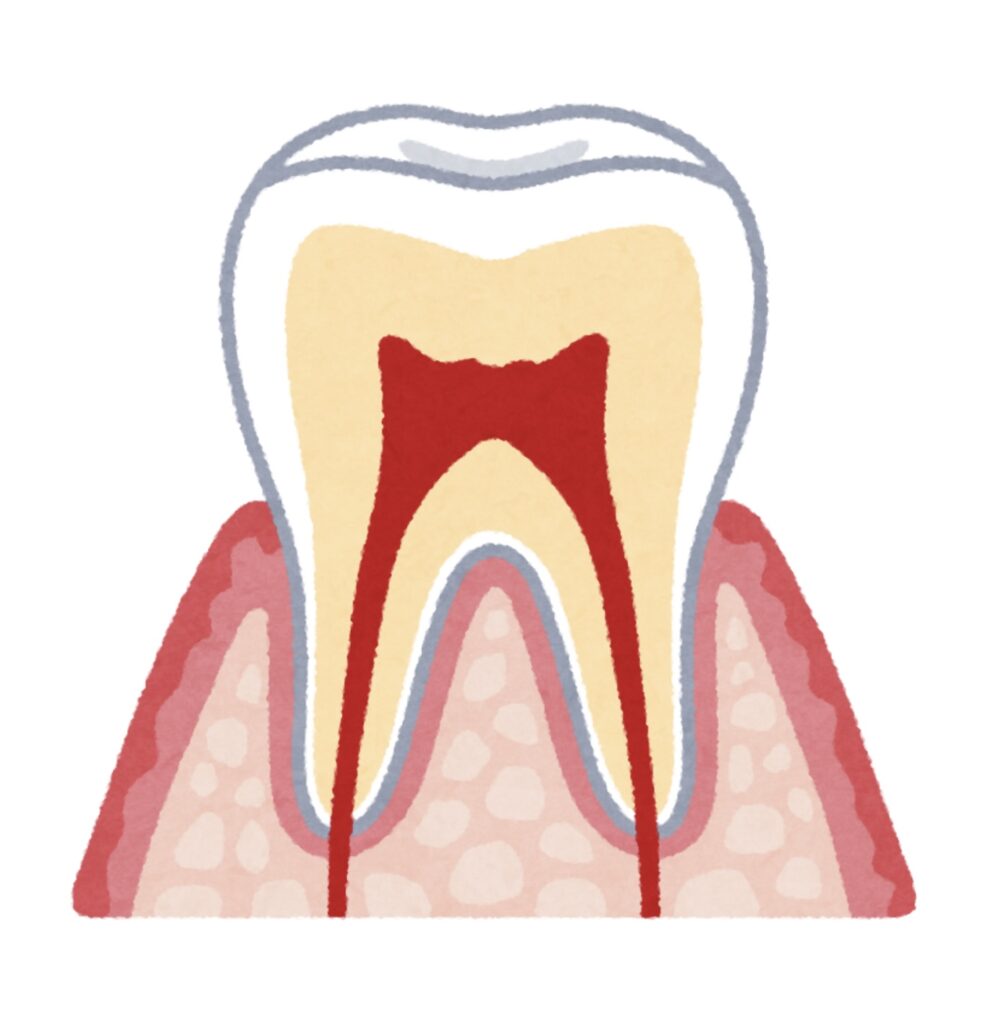

歯根吸収とは、歯の根(歯根)が短くなる現象のことを指します。

歯は顎の骨の中にしっかりと支えられていますが、外から力が加わったり、炎症が起きたりすることで、歯根の一部が吸収されることがあります。

歯根吸収にはいくつか種類がありますが、矯正治療と関連が深いのは

「外部歯根吸収」と呼ばれるタイプです。